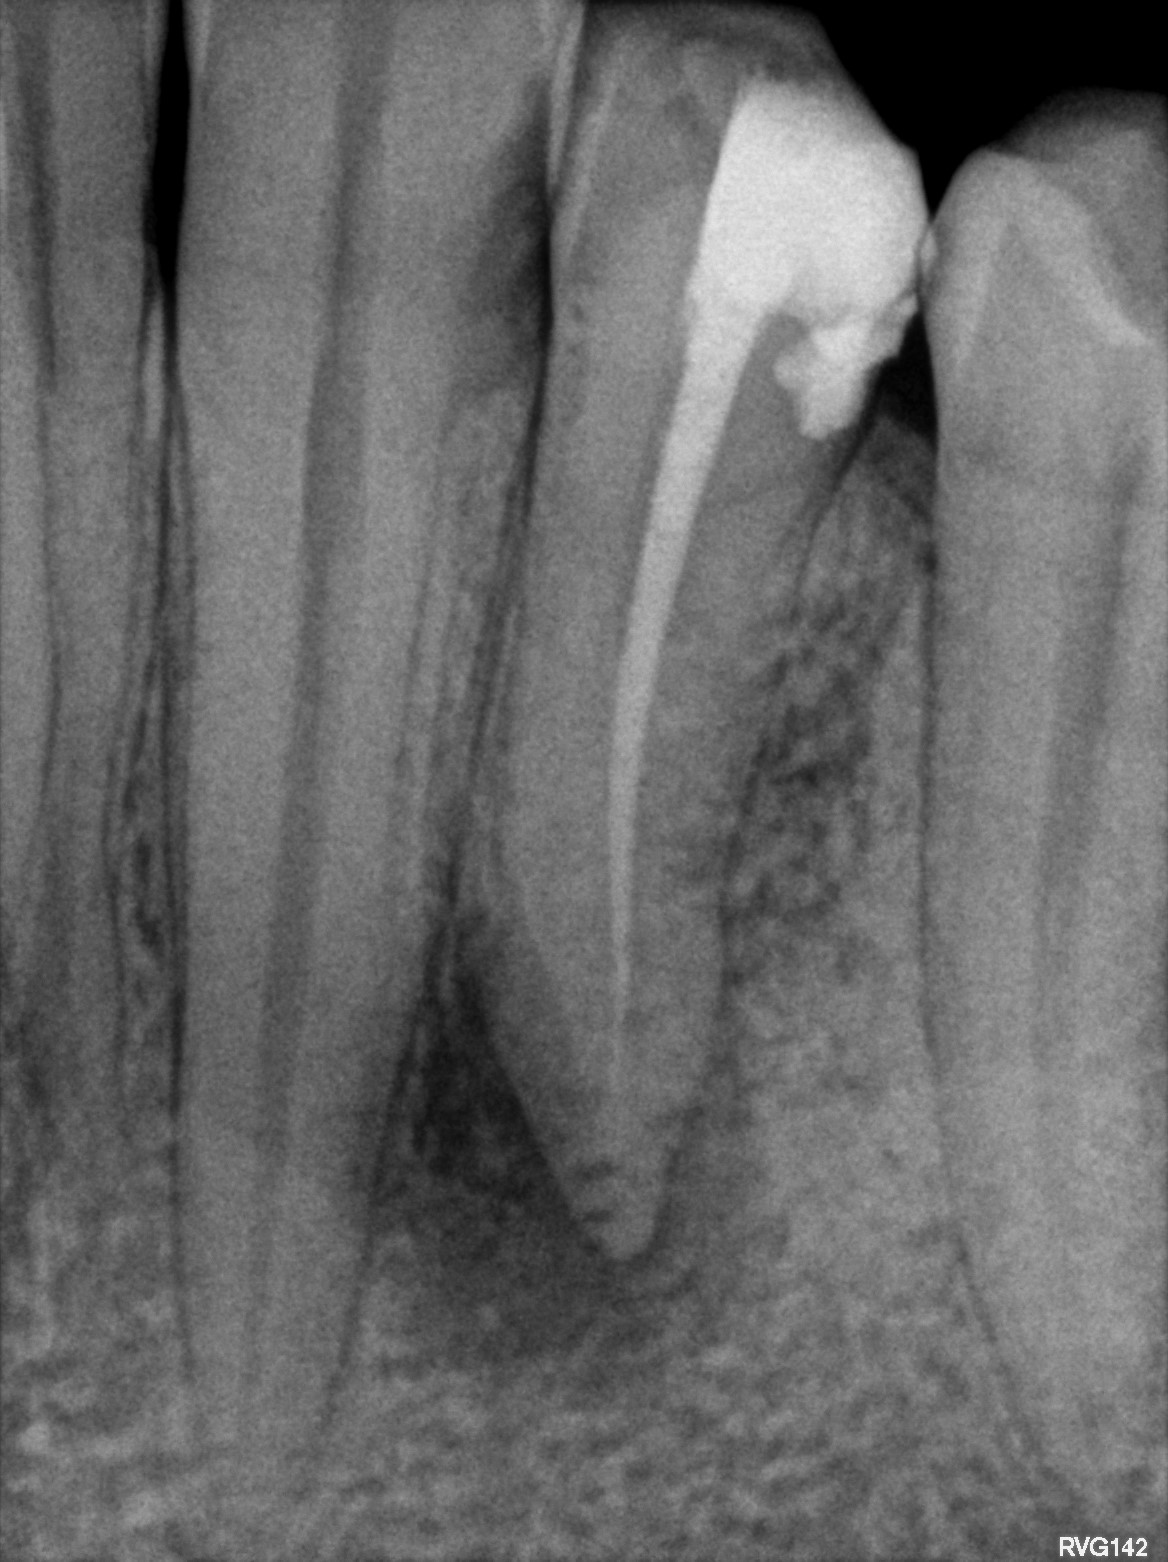

Fig 2: Pre-op radiograph

A patient presented with a large draining buccal abscess that showed a large peri apical lesion with an incompletely obturated canal on the pre-operative intraoral radiograph.